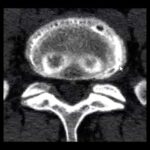

Uma das coisas que pode acontecer é a fibrose. A fibrose é uma cicatriz perto do nervo e essa fibrose perto do nervo pode começar a dar dor e incômodo. Geralmente, o paciente fala que é um tipo de dor diferente do que ele sentia antes da cirurgia. Obviamente, a cirurgia mais comum para esses quadros é uma laminectomia. O paciente tem um canal estreito e a coluna está apertando, geralmente em pacientes com mais idade, sendo 70 anos a idade mais comum, e ele começou a ter dificuldade para andar, formigamento nas pernas. Indica-se esse procedimento e, ao descobrir a coluna dele, inicia-se o processo cirúrgico. Mas pode estar acontecendo essa fibrose.

Outra coisa que acontece bastante com esses pacientes, muitas vezes associado à anatomia – alguns precisam, não todos – inclusive, hoje em dia, já se acostuma com a minoria operar para artrodese, porque quando você muda a anatomia, o peso vai para outro local, além da sacroileíte, que é uma alteração na articulação da junção da coluna e pode começar a causar uma dor diferente do que ele sentia antes da cirurgia.

Junto com isso, o paciente pode ter algumas artroses na faceta, como se fosse entre uma vértebra e outra, causando também uma alteração na coluna lombar. Além disso, toda atenção com o paciente deve ser levada em consideração. A gente divide a especialidade para ajudar nossa vida, mas nosso corpo é todo conectado. Muitos desses pacientes têm um canal estreito e outras alterações de quadril. Muitas vezes, quando começa a melhorar essa parte da coluna, ele aumenta um pouco a mobilidade e começa a sentir essas outras dores que estavam ali, mas como ele se mobilizava muito pouco. Então é importante conversar bastante antes, entender o que pode acontecer, os incômodos que acontecem depois da cirurgia.